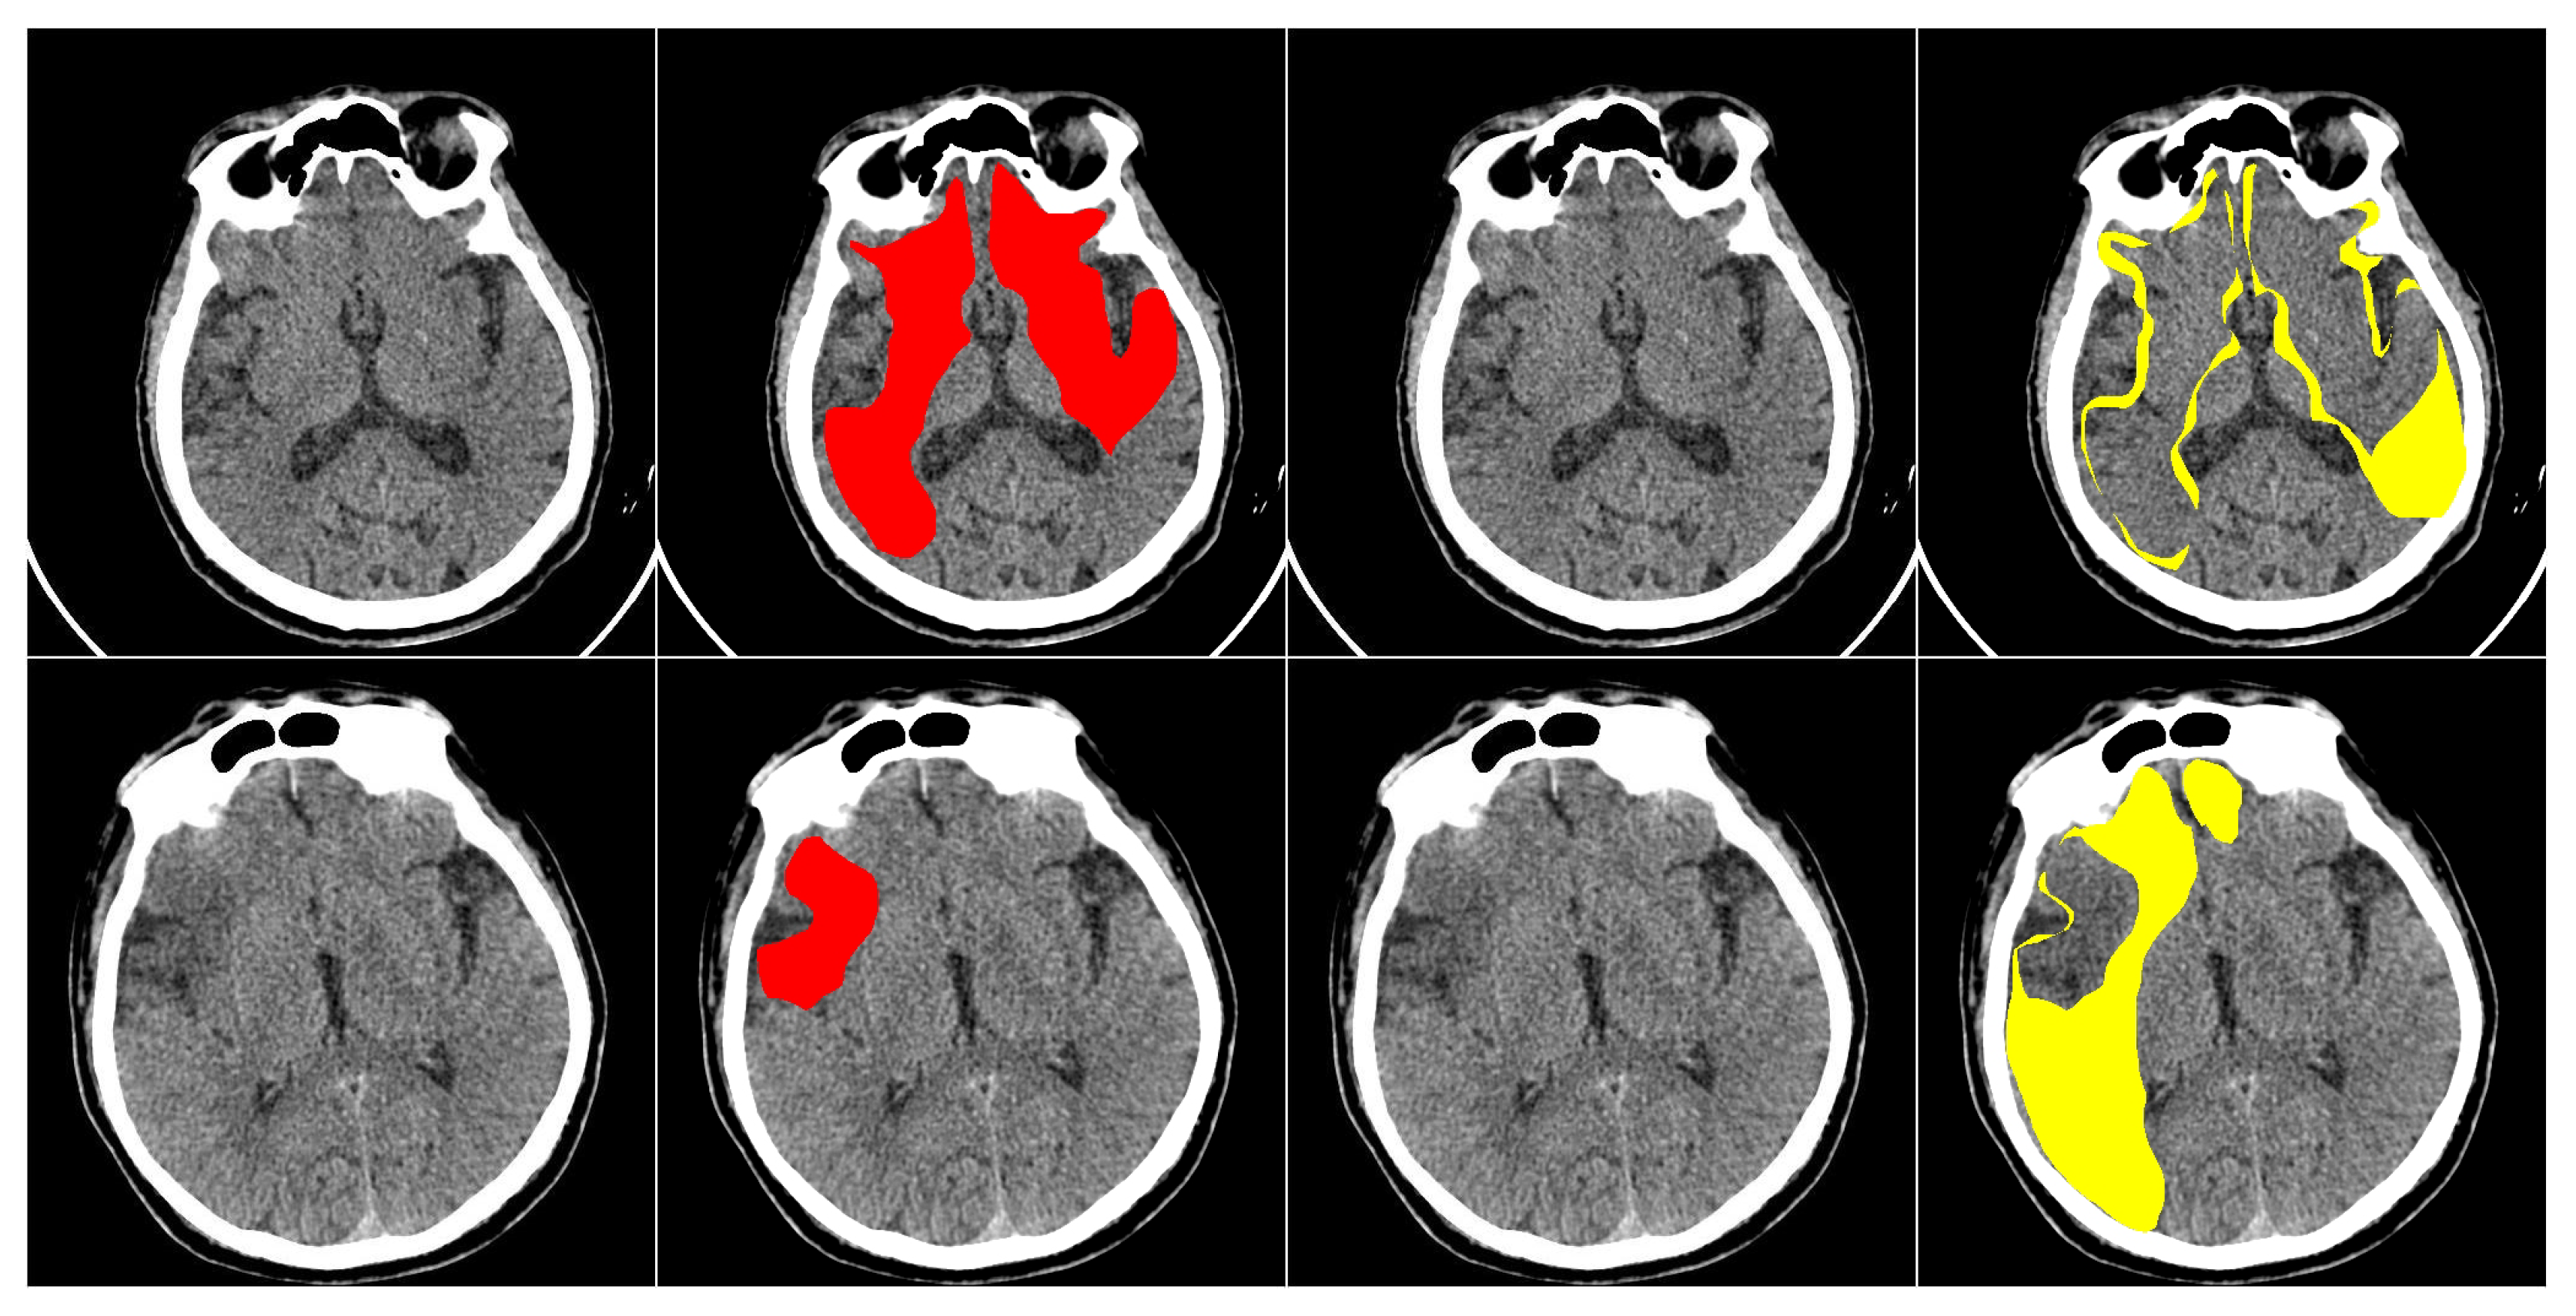

This study primarily focuses on enhancing the performance of multiclass segmentation in brain CT images. The input image is segmented into three regions: ischemic core, penumbra area, and background. The segmentation model produces three output masks, each corresponding to a specific region, with the label “1” representing a significant region and “0” otherwise (Figure 1).

The dataset contains anonymous CT scan results from 112 patients who were hospitalized during the acute phase of ultra-early ischemic stroke within 24 h of the onset of the first symptoms. It includes three classes of labeled regions: ischemic core, penumbra, and background. The images were annotated by an experienced radiologist, who outlined the penumbra and core regions on each relevant slice. In total, the dataset includes 10,165 images, with 8376 slices used as the training set, 980 images reserved for validation (hyperparameter tuning), and 809 slices used for testing. Each image in the dataset has a resolution of 512 × 512 pixels. An example of images from the dataset is shown in Figure 5.